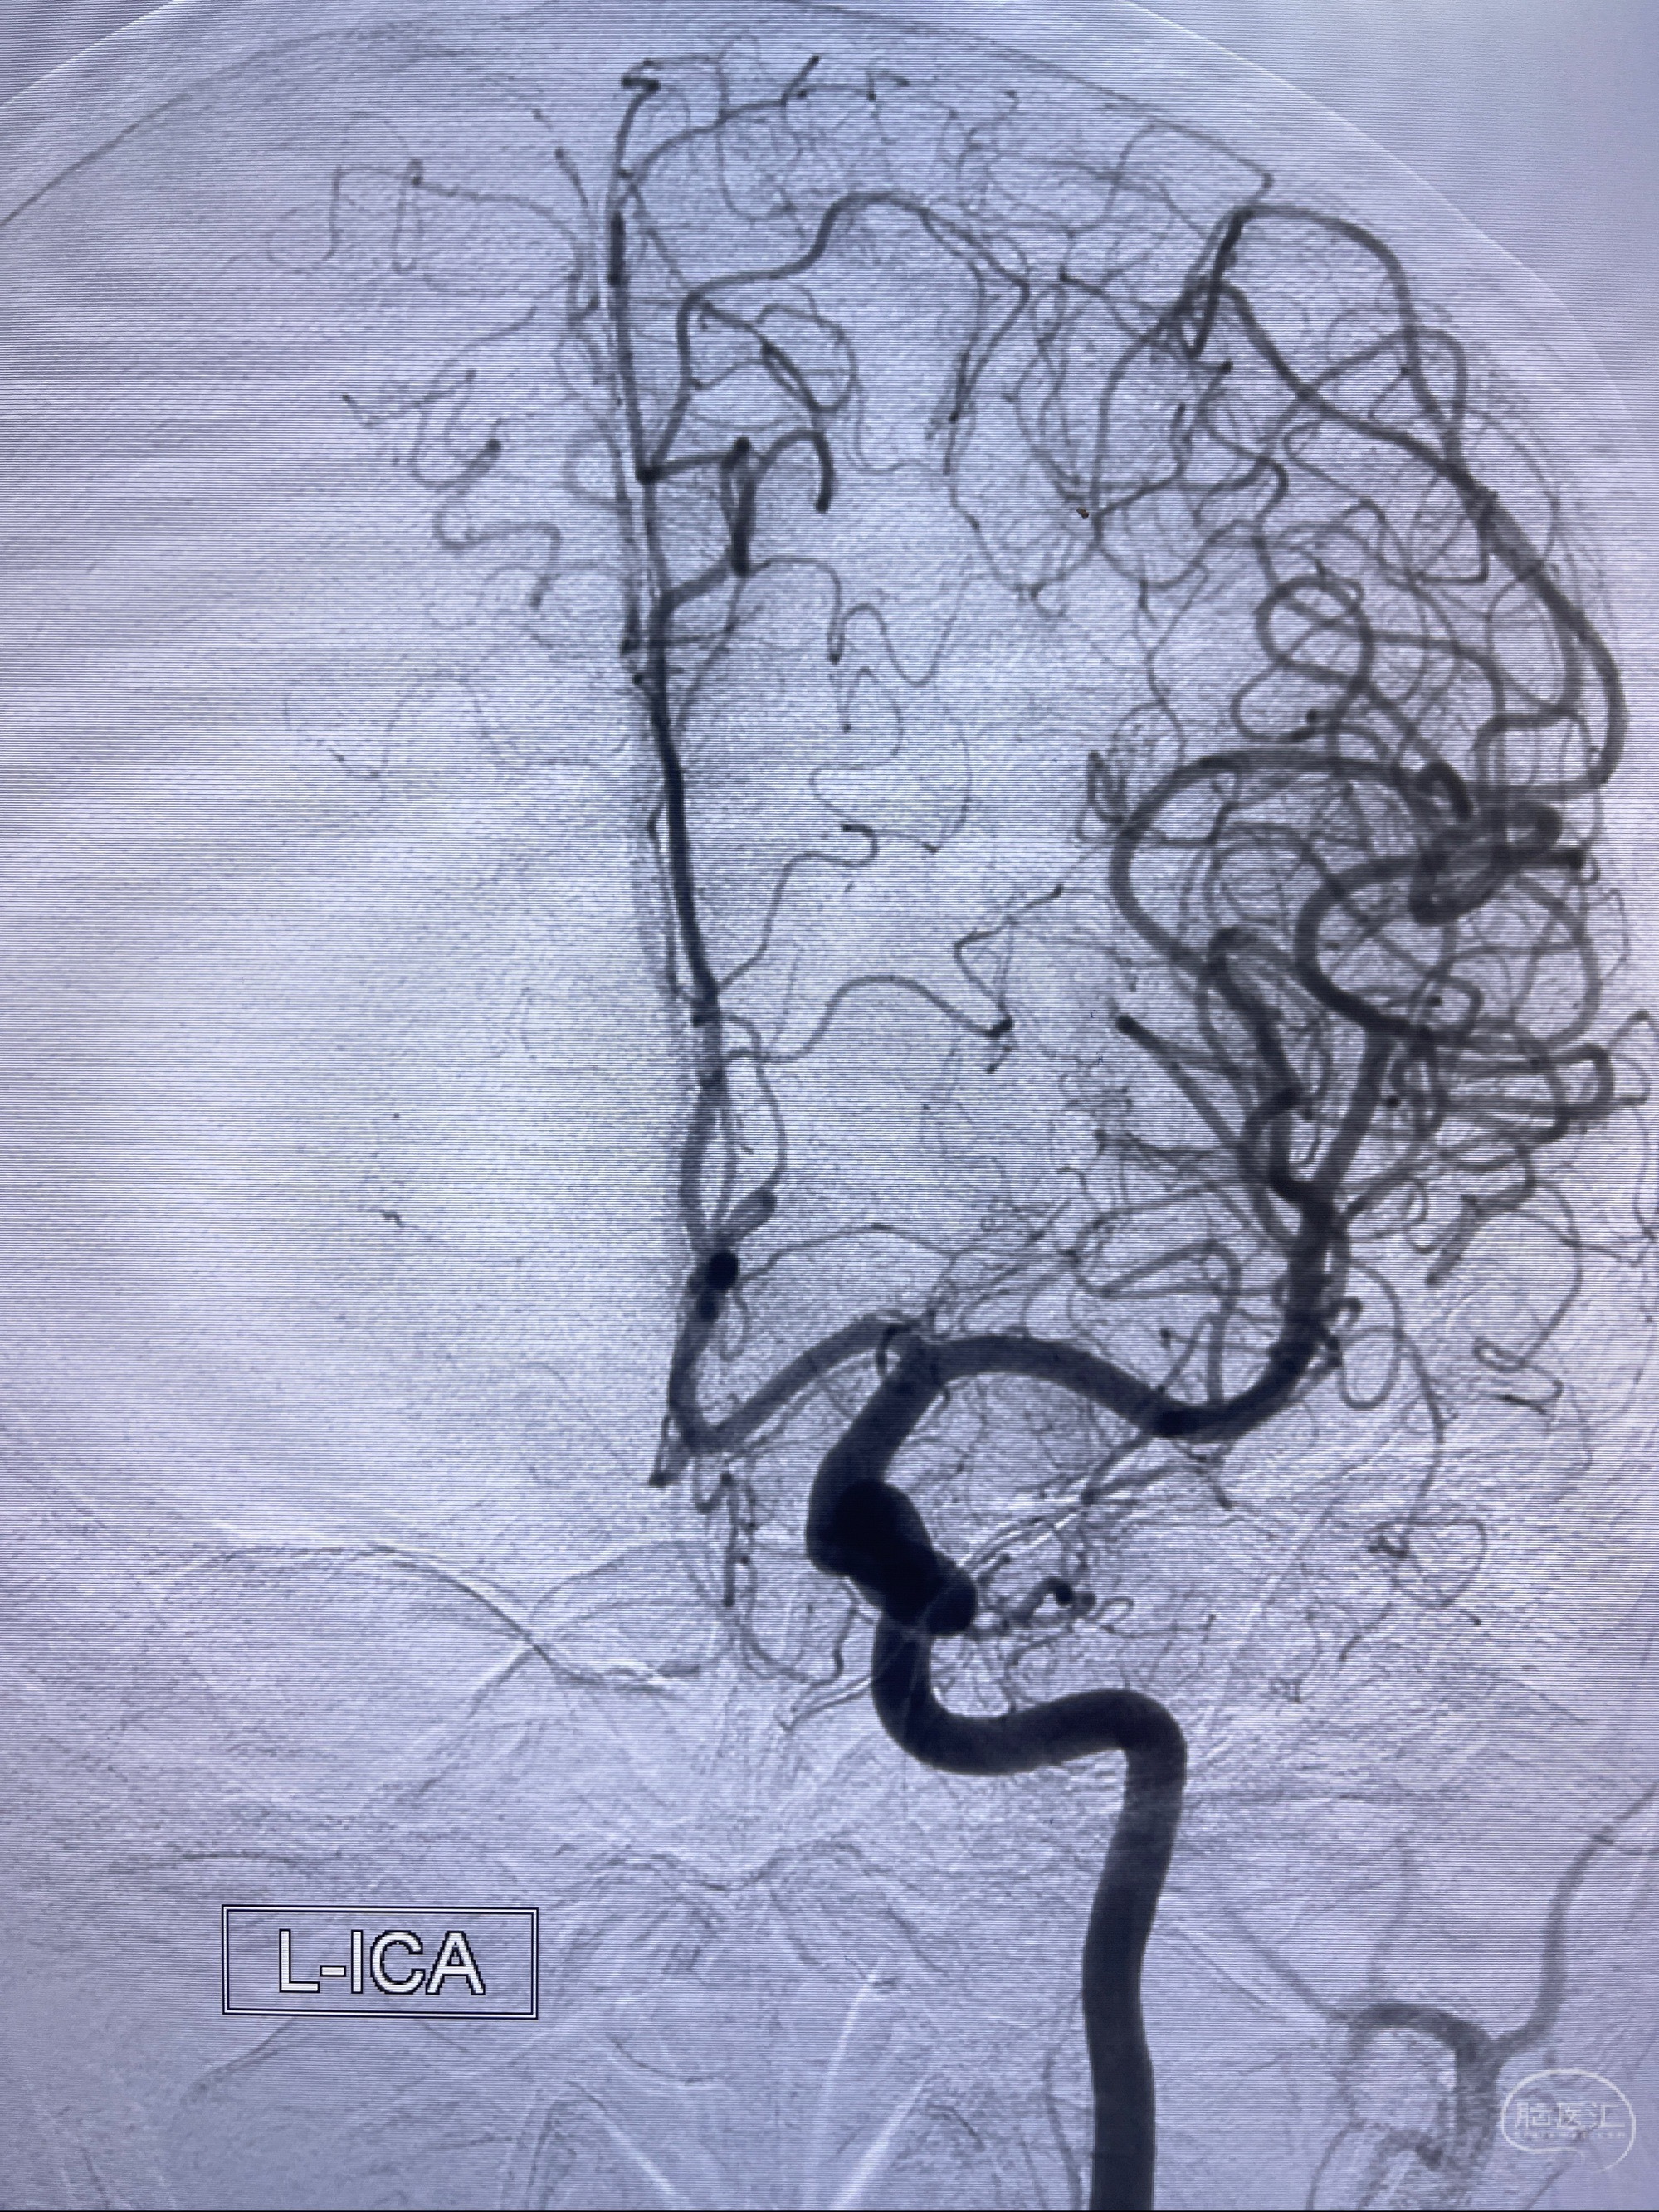

2023-07-27全脑血管造影:双侧颈内动脉眼动脉段动脉瘤,右侧较大

2023-08-01全麻下行双侧颈眼动脉瘤支架辅助栓塞

- pipeling4.5-20mm

- pipeline 4.0-20mm